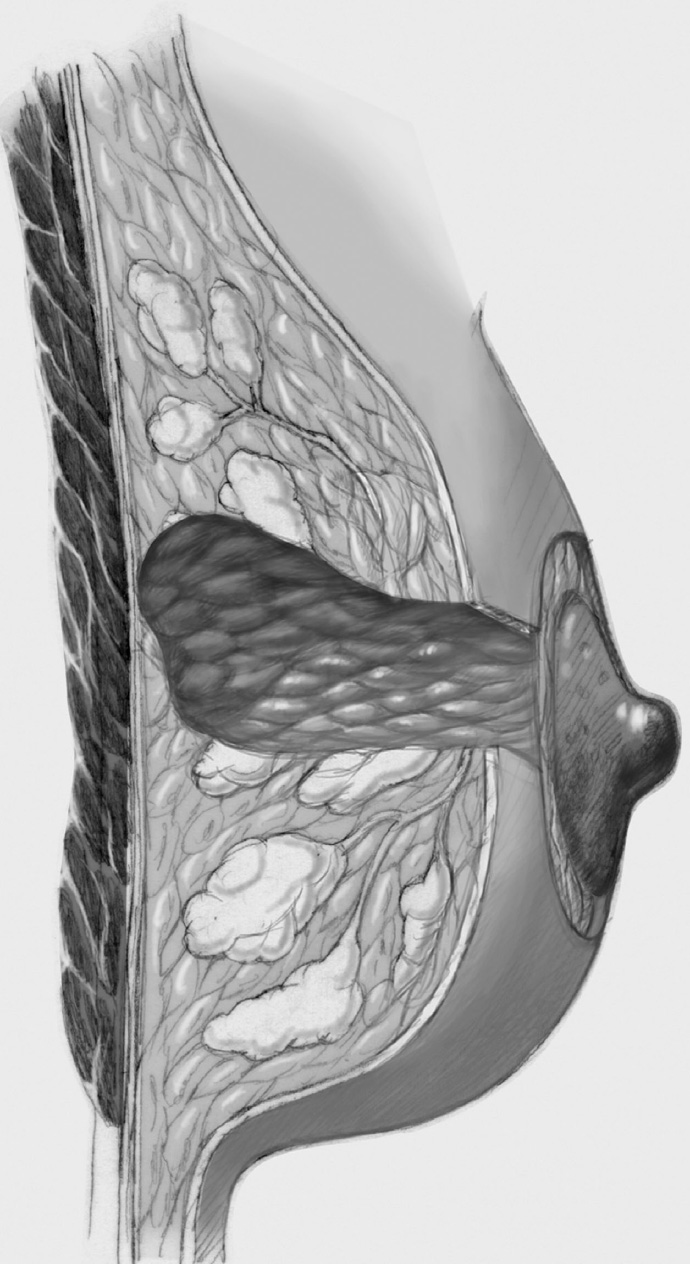

Complex and Oncoplastic Breast-Conserving Treatment

The same principles apply as in simple breast-conserving treatment though the size of the tumor necessitates more extensive segmental resection or even quadrant resection, which requires internal breast reconstruction with more complex defect cover by lobes of the breast. Often, more skin has to be resected to match the reduction in the size of the breast produced by the operation. Only the last step of periareolar de-epithelialization and nipple repositioning—that is, complex oncoplastic breast-conserving treatment—is not performed.

The skin is incised over the tumor region as far as possible (depending on surgeon, tumor size, tumor location, and subsequent treatment). A radial incision may be useful for tumors located in the lower quadrants or directly in the axillary tail of the breast. If the tumor is just beneath the skin, an island of skin over the tumor should be resected also. This can be achieved with both an elliptical semicircular incision and a radial incision. Another form is a purely periareolar incision when the tumor is in a relatively central position (see illustrations below).

The segment containing the tumor is dissected sharply with dissecting scissors or electrocautery; an adequate initial resection margin should be obtained under digital control or sonographic direct visualization. A specimen sonogram or mammogram is performed when needed.

After complete resection of the tumor area, a drain is placed in the wound cavity.

The former tumor region is marked with titanium clips (usually three clips for spatial orientation).

The adjacent parenchyma is mobilized subcutaneously so that the defect can be filled with lobes of breast tissue. Mobilization means exposing the breast relative to the skin or muscle to achieve adequate mobility of < 25% or > 25% as required.

Tension-free approximation for complete intramammary cover of the defect

The wound is closed in two layers, suturing the skin with an absorbable monofilament (3–0 or 4–0) suture.

Special Technique Simple, Complex, and Oncoplastic Breast-Conserving Surgery